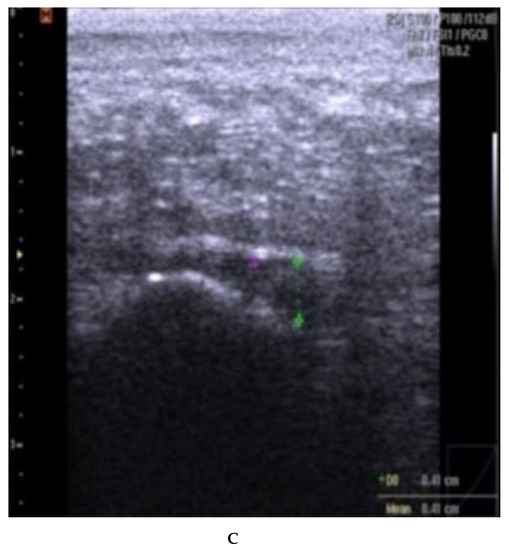

Fascia thickness and echogenicity. All patients had an increased plantar fascia thickness (3.50–8.0 mm) at baseline when measured with MSKUS, and all had hypo-echogenicity. There was a significant difference in the reduction of the plantar fascia thickness between the two groups at 4 weeks follow-up in favor of CSI + TUS (p = 0.004, Table 5), as also shown in Figure A1 and demonstrated in ultrasound images in Figure A2 and Figure A3. At the 12-week follow-up, plantar fascia thickness was significantly higher in the CSI + TUS group (p = 0.012), with an insignificant difference in the decrease between both groups (p = 0.216).

Echogenicity change (Figure A2 and Figure A3) from hypoechoic to iso- or hyperechoic was statistically significant in both groups at 12-week follow-up, but no significant difference was found between the groups (p = 0.208; Table A1).

(A–C): plantar fascia thickness and echogenicity before, after 4 weeks, and 12 weeks follow-up (ESWT). (A). Plantar fascia thickness (0.53 cm) and echogenicity (hypoechoic) before ESWT; Ankles are in 90 dorsiflexion;. Images obtained just medial to the midline, at the proximal end of the plantar fascia, distal to its origin, from the medial tubercle of the calcaneus; Thickness of the plantar fascia was measured from the base of the medial calcaneal tubercle, where a bright echogenic line was easily visible. (B). Plantar fascia thickness (0.51 cm) and echogenicity (hypoechoic) after 4 weeks. (C). Plantar fascia thickness (0.48 cm) and echogenicity (hypo-echoic) after 12 weeks.